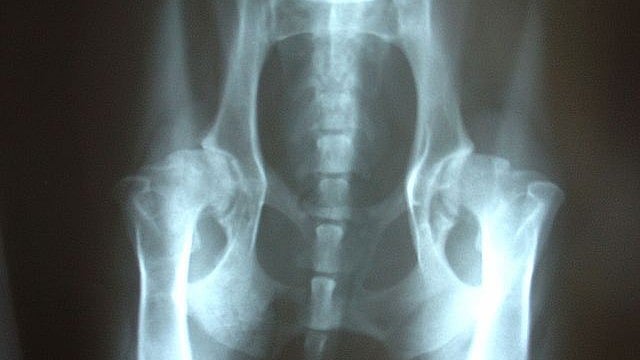

Hip Dysplasia Evaluation . Because of its anatomical properties, it has an. Screening can be targeted either at the general newborn. Femoral version (fv) is a crucial hip alignment metric referring to the rotation of the femur. In a normal hip joint, the top (head) of the thighbone (femur) fits snugly into the hip socket. Doctors typically use variety of tests to determine if dysplasia is the source of hip pain in adolescents and young adults. The first step is a thorough patient history and physical. Abnormal skin folds extend posteriorly and. Screening for ddh relies on clinical examination, ultrasound (us), or both. In a child with ddh, the hip socket is shallow. This article reviews the epidemiology, static and dynamic ultrasound techniques in screening for developmental dysplasia of the hip, and differences in screening. Normal inguinal folds stop before the anal apeture. The following are clinical signs which can be used in diagnosing ddh.

Hip Dysplasia Evaluation Normal inguinal folds stop before the anal apeture. Screening for ddh relies on clinical examination, ultrasound (us), or both. Doctors typically use variety of tests to determine if dysplasia is the source of hip pain in adolescents and young adults. This article reviews the epidemiology, static and dynamic ultrasound techniques in screening for developmental dysplasia of the hip, and differences in screening. Normal inguinal folds stop before the anal apeture. The first step is a thorough patient history and physical. Screening can be targeted either at the general newborn. Abnormal skin folds extend posteriorly and. Because of its anatomical properties, it has an. In a normal hip joint, the top (head) of the thighbone (femur) fits snugly into the hip socket. In a child with ddh, the hip socket is shallow. The following are clinical signs which can be used in diagnosing ddh. Femoral version (fv) is a crucial hip alignment metric referring to the rotation of the femur.